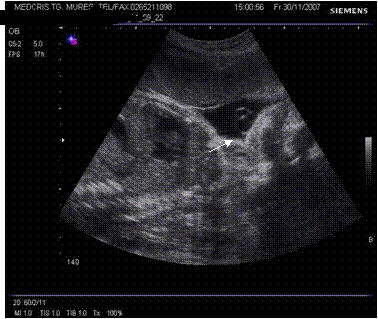

Fig. nr.217. Placenta praevia centrala la 15 saptamani ( linia indica raportul placenta praevia cu orificiul cervical intern)

Fig. nr.218. Placenta praevia complet centrala , la aceeasi sarcina ca in figura precedenta, dar la 28 saptamani gestationale